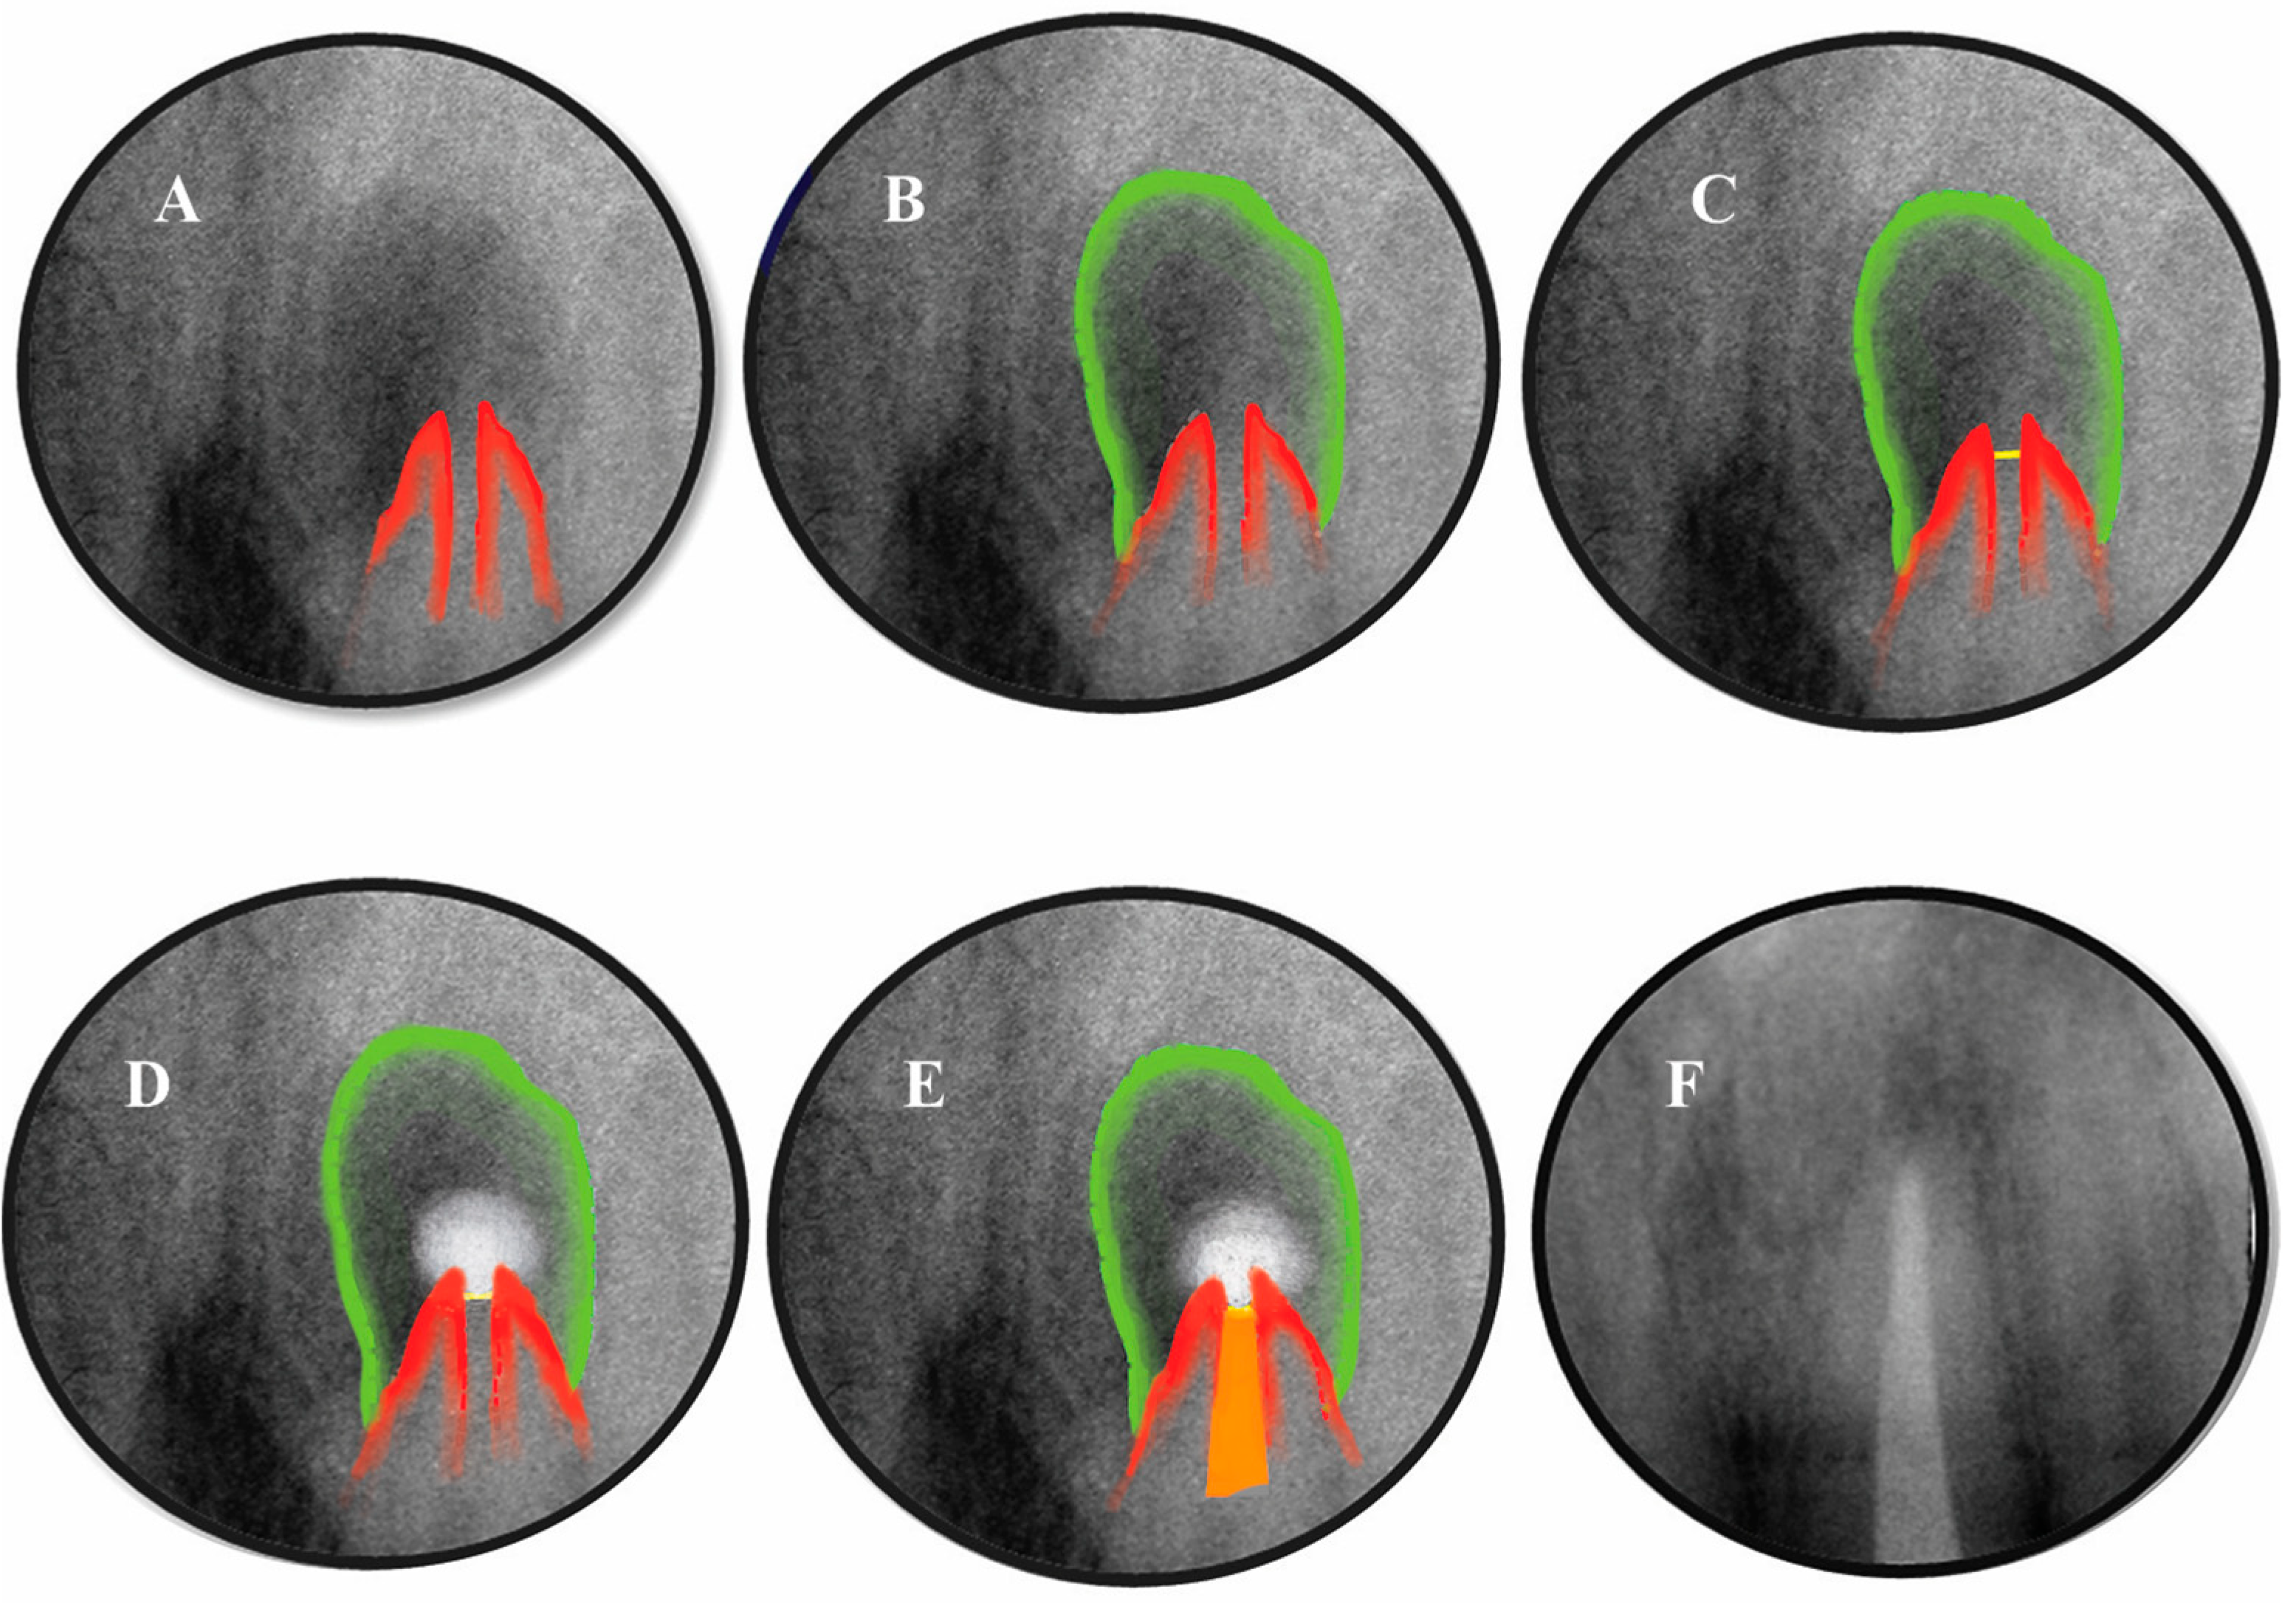

5. Apical Plug in Teeth with Periapical Lesions

5.1. Apical Plug in Teeth with Apical Resorption and “Open Apex”

5.2. Apical Barrier

- Gusiyska, A.; Ilieva, R. Nanosize Biphasic Calcium Phosphate used for Treatment of Periapical Lesions. Int. J. Curr. Res. 2015, 7, 11564–11567. [Google Scholar]